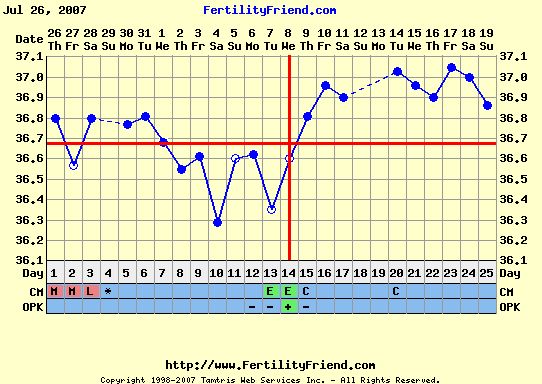

Ha valaki nem tudná "kiolvasni", mit lát, segítek: az első képen a drágánk feje jobb ldalt (a másikon is

) , aztán a kis teste, a cicije felett a pici folt az egyik keze, aztán egy nagy pocak, majd valahogy a lábai (egy pár lábujjacskája látható!

)

A másik képenközelebbről van a buksija, lehet látni a nóziját, meg az éppen csókra álló száját!!

Ja, és amikor uh-zott a doki, kitátotta a száját, vissza is játszotta BB, mondta, hogy tök érdekes, még ilyen pici, és nyitogatja a száját! Hát egész nap vigyorogtunk, úgy örültünk! Tényleg nagyon jó volt látni!

Ő a kisfiúnk, csak így tudtuk lefotózni, ennél jobban nem mutatta a kis pofiját.

Ő a kisfiúnk, csak így tudtuk lefotózni, ennél jobban nem mutatta a kis pofiját.